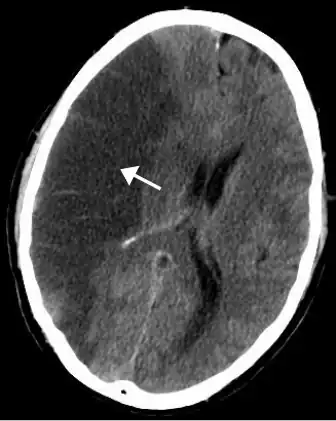

![]() | |

| CT scan of the brain showing a massive, prior right-sided ischemic stroke from blockage of an artery. Changes on a CT may not be visible early on.[1] | |

The most significant risk factor for stroke is high blood pressure.[7] Other risk factors include high blood cholesterol, tobacco smoking, obesity, diabetes mellitus, a previous TIA, end-stage kidney disease, and atrial fibrillation.[2][7][8] Ischemic stroke is typically caused by blockage of a blood vessel, though there are also less common causes.[13][14][15] Hemorrhagic stroke is caused by either bleeding directly into the brain or into the space between the brain's membranes.[13][16] Bleeding may occur due to a ruptured brain aneurysm.[13] Diagnosis is typically based on a physical exam and supported by medical imaging such as a CT scan or MRI scan.[9] A CT scan can rule out bleeding, but may not necessarily rule out ischemia, which early on typically does not show up on a CT scan.[10] Other tests such as an electrocardiogram (ECG) and blood tests are done to determine risk factors and possible causes.[9] Low blood sugar may cause similar symptoms.[9]